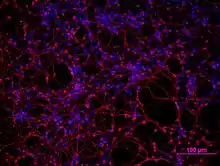

Fujifilm Cellular Dynamics, Inc. (FCDI) is a large scale manufacturer of human cells, created from induced pluripotent stem cells, for use in basic research, drug discovery and regenerative medicine applications.

FCDI offers several terminally differentiated cell types as catalog products: iCell® Cardiomyocytes, iCell Neurons, iCell Endothelial Cells, and iCell Hepatocytes. CDI's MyCell® Products portfolio enables customer-provided donor samples to be reprogrammed, gene edited, and differentiated. The company also has several prototype products derived from pluripotent stem cells, including iCell Cardiac Progenitors, iCell Hematopoietic Progenitors, iCell Astrocytes, and iCell Skeletal Myoblasts.

At least 5 of the top 10 Leading Causes of Death in the United States have a vascular component related to their disease.[18] Endothelial cells (cells that line the interior of blood vessels and allow nutrients to pass back and forth to the body's organs and tissues) play an important role in the study of vascular contributions of many leading causes of death. iCell Endothelial cells were launched as a tool to model vascular biology. Other types of endothelial cells are available from ATCC and Life Technologies. iCell Hematopoietic Progenitor Cells are multipotent progenitor blood cells that can give rise to many different types of blood cells that can then be used for a variety of research purposes, including cell therapy, autoimmune disease, and cancer research.